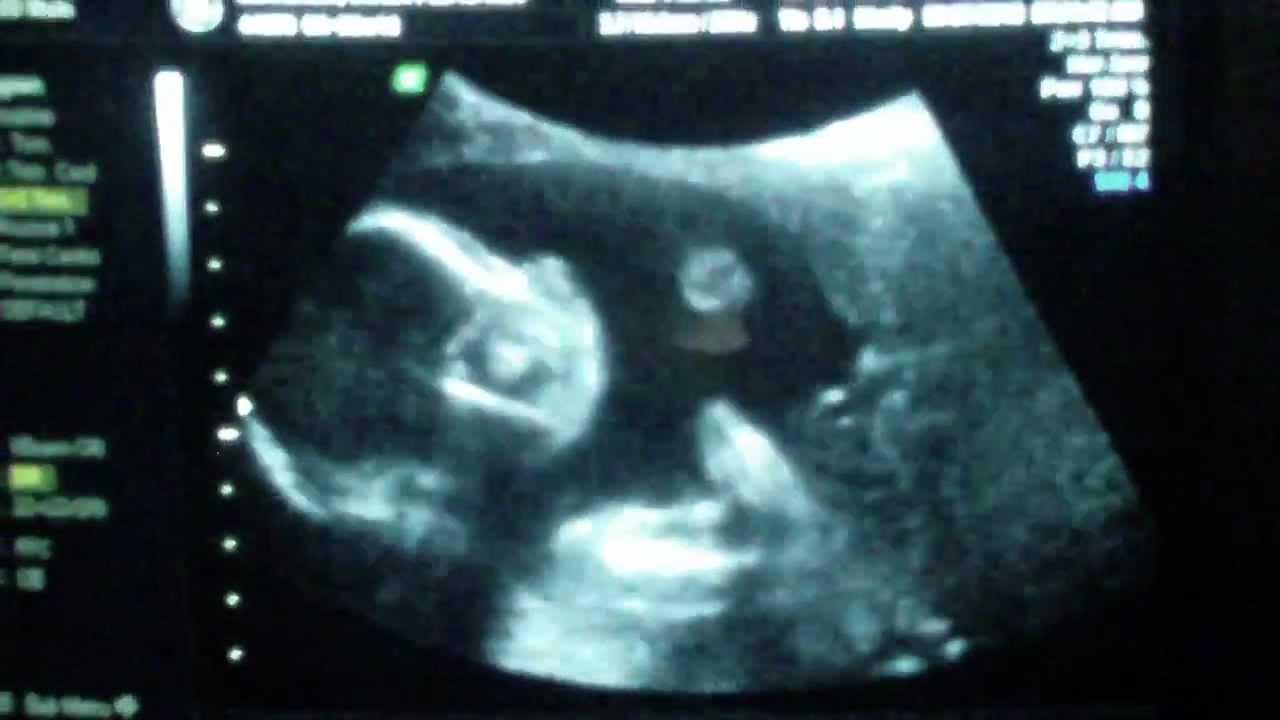

Το θαύμα της εγκυμοσύνης. 14 εβδομάδων έμβρυο χειροκροτεί όταν οι γονείς του τραγουδούν!